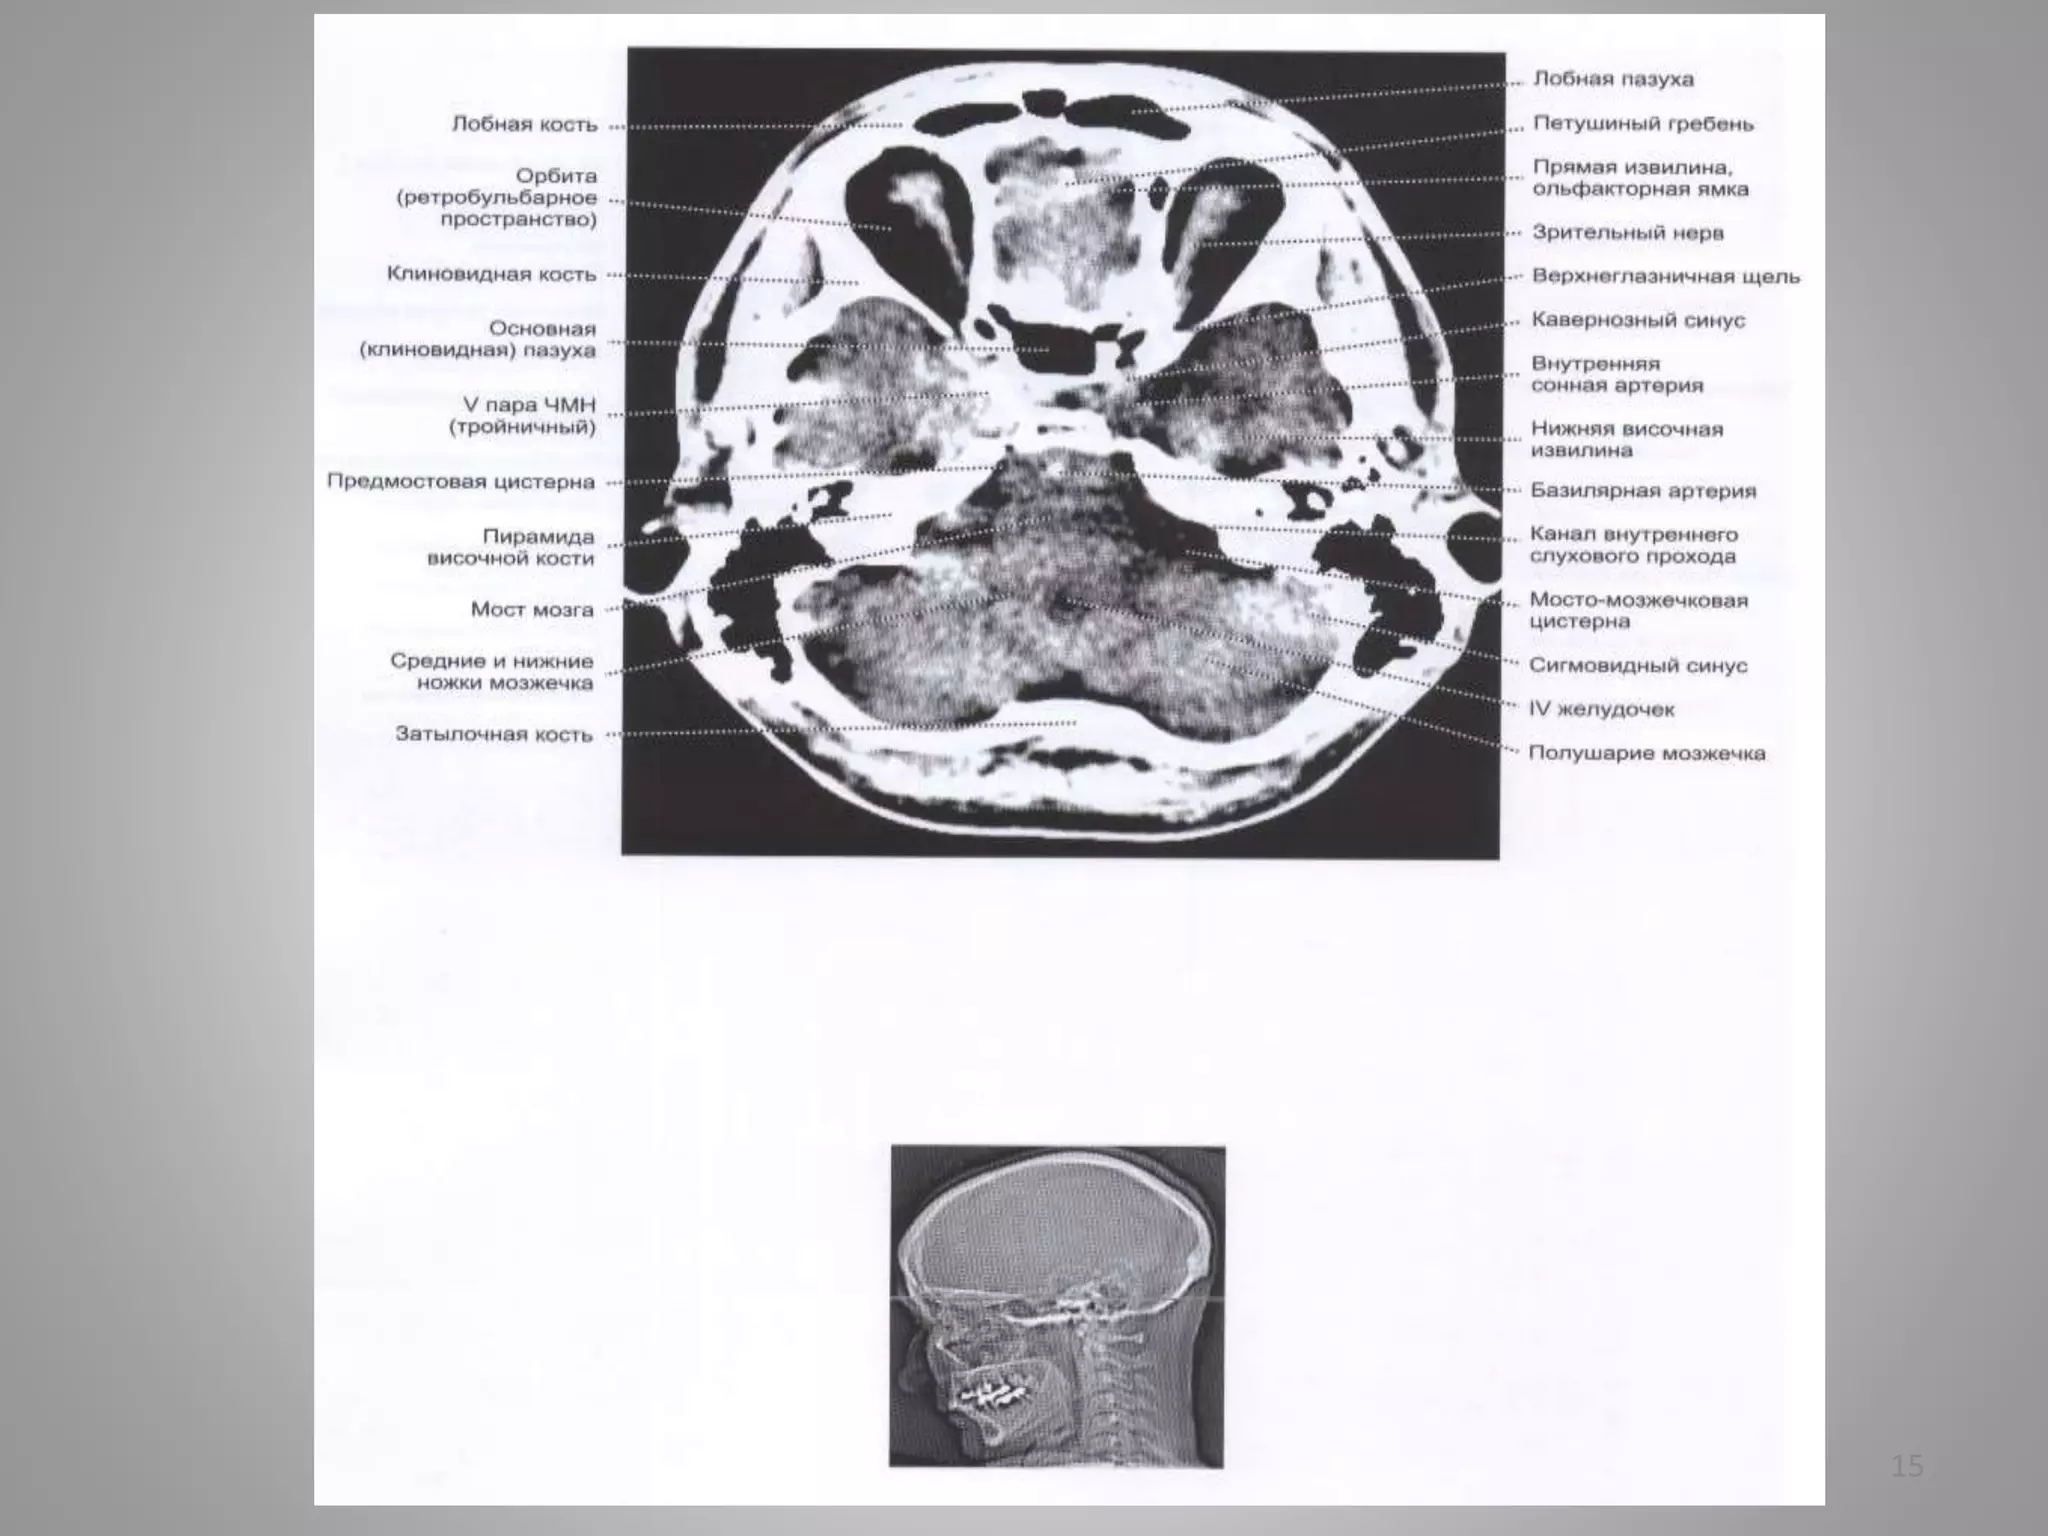

Деякі особливості КТ

79